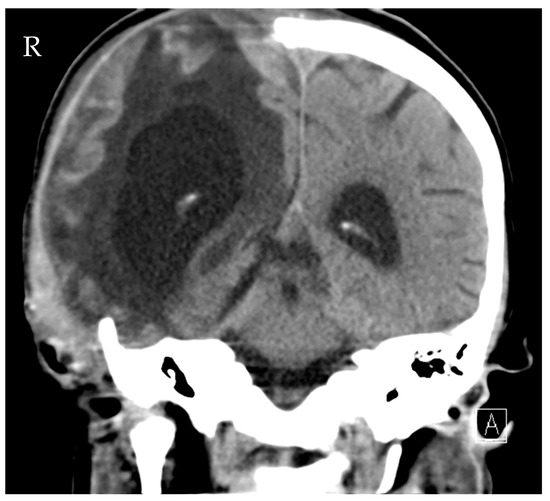

A 16-year-old girl was admitted to the emergency department after a car crash. By the time of admission, she was intubated, haemodynamically unstable and showed anisocoria. Haemodynamic instability was due to pneumothoraxes on both sides. Pleural drainage tubes were inserted immediately, and the circulation improved. A computed tomography scan showed polytrauma with severe craniocerebral injury and traumatic dissection of the right internal carotid artery. Moreover, there were severe bilateral pulmonary contusions, the laceration of the spleen and liver, a ruptured bladder with massive venous bleeding and an unstable pelvic fracture. Damage control surgery was performed subsequently with splenectomy, the opening of the bladder and the packing and temporary closure of the abdomen. The fractured pelvis was stabilized with an external fixator, and an intraventricular catheter was inserted to monitor the intracranial pressure (ICP). Only a few hours after the initial procedure, the patient presented with increasing ICP and dilated pupils on both sides. Another computed tomography scan revealed malignant, right hemispheric stroke due to the traumatic dissection with progressive cerebral oedema and signs of herniation (Figure 1). Decompressive craniectomy was conducted immediately to control the ICP. Postoperatively, the patient suffered multiple epileptic seizures and exhibited increasing blood sodium levels due to central diabetes insipidus.

Figure 1.

Computed tomography of the head showing cerebral oedema and signs of herniation.